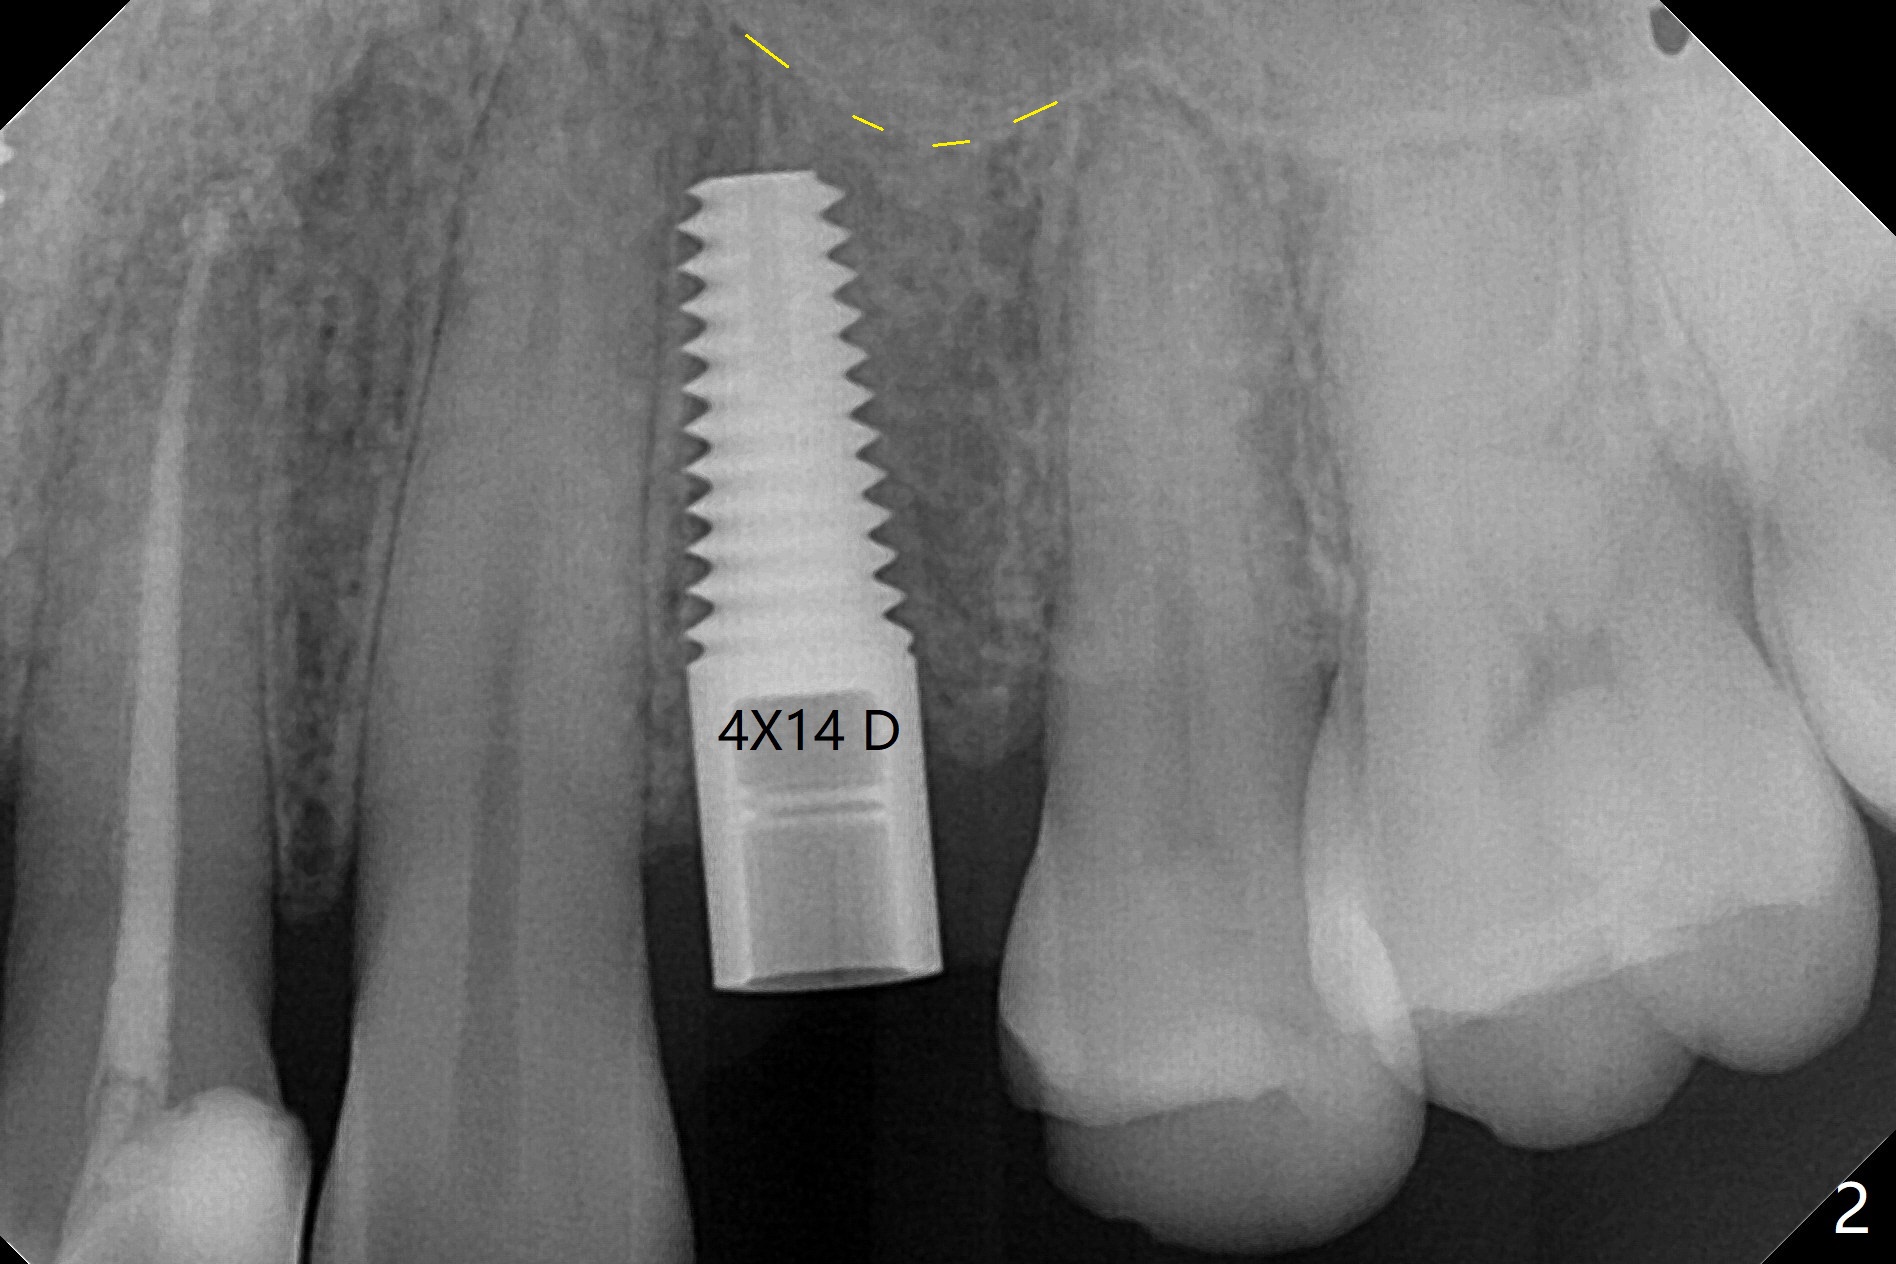

拔牙前发现患牙颊侧牙龈退缩(图一),需要软组织移植吗?拔牙后,在根尖用1,1.5,2.0 和3.0毫米骨凿打穿窦底,然后输入粘性骨粉(图四:*)。腭侧骨壁建立钻洞(有利于颊侧牙龈再生),忘了拍摄先锋钻根尖片,直接植入4x14毫米软组织水平报废植体,接近尖牙牙根(图二(黄虚线:窦底))。木已成舟,无法改变方向,又没有更长植体,只好植入同样大小植体(图三),即刻放置基台,固定骨粉和PRF膜,后者促进颊侧退缩牙龈再生,最后使用树脂敷料封闭伤口。